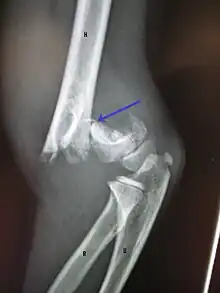

Fracture de l'extrémité inférieure

Ces fractures surviennent surtout chez l'enfant, le plus souvent par chute sur la main, coude en extension, plus rarement coude fléchi ou semi-fléchi. La zone de faiblesse est alors le cartilage de croissance. La ligne de fracture peut être supra-condylienne ou inter-condylienne (condyle latéral, épicondyle médial). Le traitement est le plus souvent chirurgical[10],[14].

Il s'agit d'une urgence, car il existe des risques importants de séquelles : l'arrêt de croissance avec inégalité de longueur et déviations, pseudarthrose, préjudice esthétique, ostéonécrose de fragment osseux, et pour la fracture de l'épicondyle médial une « griffe cubitale » (parésie des deux derniers doigts) par atteinte du nerf ulnaire [10],[14].